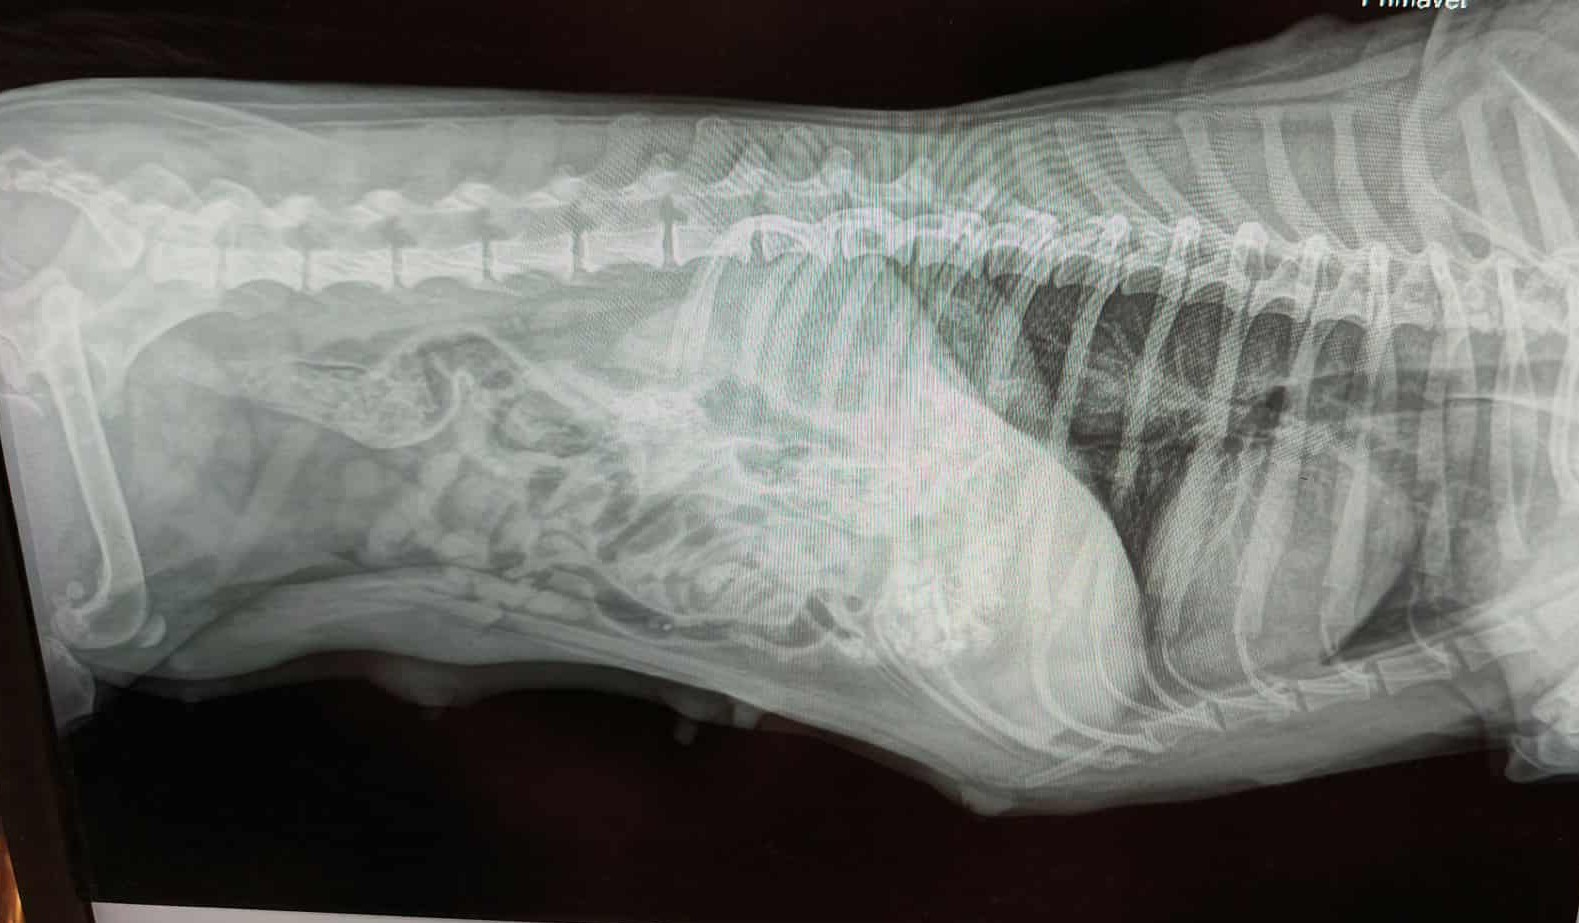

Am Donnerstag Abend kam ein Notruf bei mir an von einem überfahrenen Dackel Rüden. Obwohl mein kleiner Sohn auch krank im Bett lag, konnte ich nicht nein sagen, weil so spät am Abend niemand anderer geholfen hätte. Ich war in einer halben Stunde beim Dackelchen und nach weiteren 1,5 Stunden Fahrt in der Klinik. Nach den Röntgenaufnahmen bekam ich schlechte Nachrichten: diaphragmatic hernia. Das heisst, vom heftigen Schlag beim Überfahren rutschte sein (mit Futter voller Magen) in die Brusthöhle auf.

Endlich fand sie eine andere Klinik, ich musste blitzschnell da sein und sobald wir da waren, ging das Hündchen in den OP-Raum und nach 3 nervenaufreibenden Stunden war die OP fertig. Er hat die OP gut überstanden, trotzdem konnte ich mich nicht ruhig zurücklehnen, da weitere schreckliche Befunde zum Vorschein kamen: seine Leber riss und Teile fielen ab. Außerdem ist die Milz gerissen. Sein Beckenknochen ist gebrochen. In seiner Luftröhre befand sich etwas Blut, was Anlass zur Sorge gibt, da er im Falle einer Lungenblutung nicht mehr zu retten wäre. Um dies jedoch zu verhindern, erhielt er ein Blutgerinnungsmittel, einen Blutdrucksenker und ein Schmerzmittel.